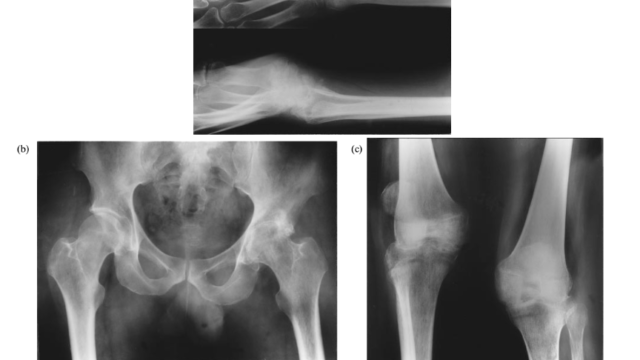

整形外科

2